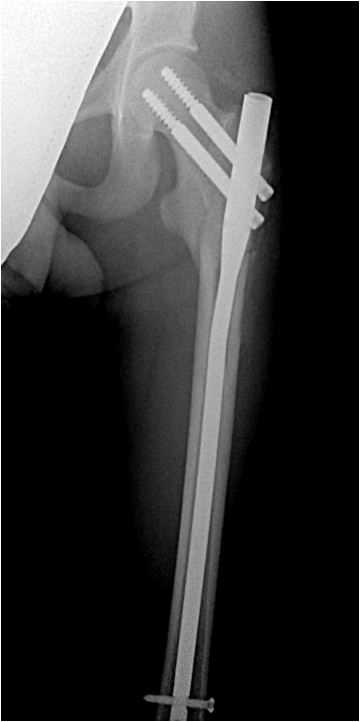

Стержень перелом

Стержень перелом 108 фотографий